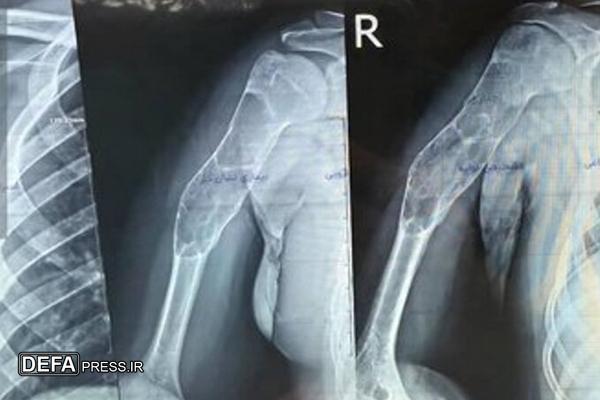

«شهریار خوشبخت»، جراح و متخصص ارتوپدی هم درباره این عمل جراحی گفت: با توجه به وجود توده کیستیک وسیع در بازوی بیمار، تیم جراحی توانست به مدت سه ساعت پس از عملیات پلاکگذاری، توده وسیع را تخلیه و استخوان مصنوعی را جایگزین کند.

وی عنوان کرد: چنین اعمال پیچیدهای به طور معمول توسط فوق تخصصهای جراحی دست در مراکز استانها انجام میشود و خوشبختانه توانستیم برای اولین بار در شمال استان اردبیل در بیمارستان امام (ره) پارسآباد این عمل را با موفقیت انجام دهیم و اکنون بیمار با حال عمومی خوب بستری است و پس از چند روز مرخص خواهد شد.